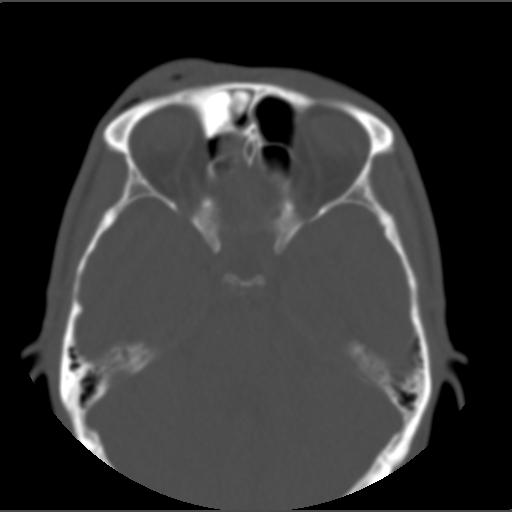

m49y外伤常规ct发现筛额窦右侧高密度块影 。

右侧额筛都内致密性高密度影,余骨皮质未见明显异常改变,右额皮下血肿伴少许积气,我想是致密影是骨瘤.

右侧额筛都内致密性高密度影,境界清楚,余骨皮质未见明显异常改变,符合骨瘤表现

右侧额筛都内致密性高密度影,境界清楚,余骨皮质未见明显异常改变,考虑额筛窦内生性骨瘤.

颅面部骨瘤一般密度致密,多发额骨及鼻窦腔壁,呈扁丘样改变.边界清楚,大部分密度均一.

1、致密型骨瘤。2、右额部头皮挫裂伤。

右额窦至密性骨瘤,右额骨皮下软组织挫伤拌积气.